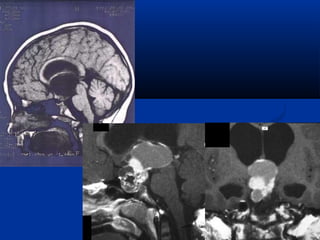

®ÆÆtt vvÊÊnn ®ÒÒ  UU ssää hhÇÇuu llμμ uu nnééii ssää,, nnggooμμii ttrrôôcc,, pphh¸tt ttrriiÓÓnn cchhËËmm,, cchhññ yyÕÕuu vvïïnngg yyªnn vvμμ ttrrªnn yyªnn,, cchhiiÕÕmm ttûû llÖÖ 33--44%% cc¸cc uu nnééii ssää,, 1155%% kkhhèèii uu ttrrªnn yyªnn..  UU tthh­­êênngg ccãã ccÊÊuu tt¹oo bbëëii ccÊÊuu ttrróócc ®ÆÆcc,, cc¸cc mm¶nnhh ccaann xxii vvμμ nnaanngg ddÞÞcchh hhooÆÆcc ccãã kkhhii ®ÇÇyy ddÞÞcchh..  KKüü tthhuuËËtt cchhôôpp CCHHTT llÇÇnn ®ÇÇuu ttiiªnn ëë VViiÖÖtt NNaamm tt¹ii ttrruunngg tt©mm MMeeddiicc SSμμii GGßßnn

TTæænngg qquuaann UUmmeenn rr¨nngg UU nnhhóó

TTæænngg qquuaann MMééttssèè tthhÓÓ ccññaa UUSSHH